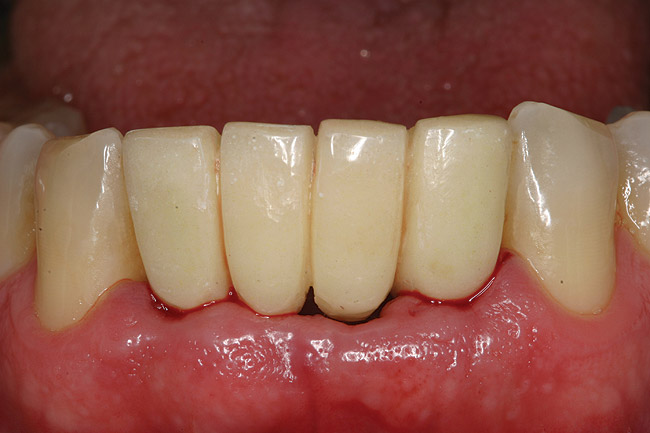

Figure 11  The final ceramo-metal restoration.

Figure 11